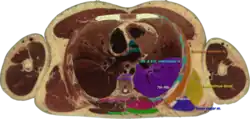

Cross section #1428 of the Visible Human Male showing the structures of the triangle of auscultation | |

The superficial floor of the triangle is formed by the lateral portion of the erector spinae muscles. Deep to these muscles are the osseous portions of the 6th and 7th ribs and the internal and external intercostal muscles.

The triangle of auscultation is useful for assessment using a pulmonary auscultation and thoracic procedures.[1] Due to the relative thinning of the musculature of the back in the triangle, the posterior thoracic wall is closer to the skin surface, making respiratory sounds audible more clearly with a stethoscope. On the left side, the cardiac orifice of the stomach lies deep to the triangle. In days before X-rays were discovered, the sound of swallowed liquids were auscultated over this triangle to confirm an oesophageal tumour. To better expose the floor of the triangle up of the posterior thoracic wall in the 6th and 7th intercostal space, a patient is asked to fold their arms across their chest, laterally rotating the scapulae, while bending forward at the trunk, somewhat resembling the fetal position.